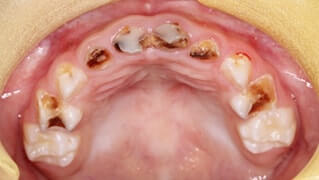

齲蝕(虫歯)